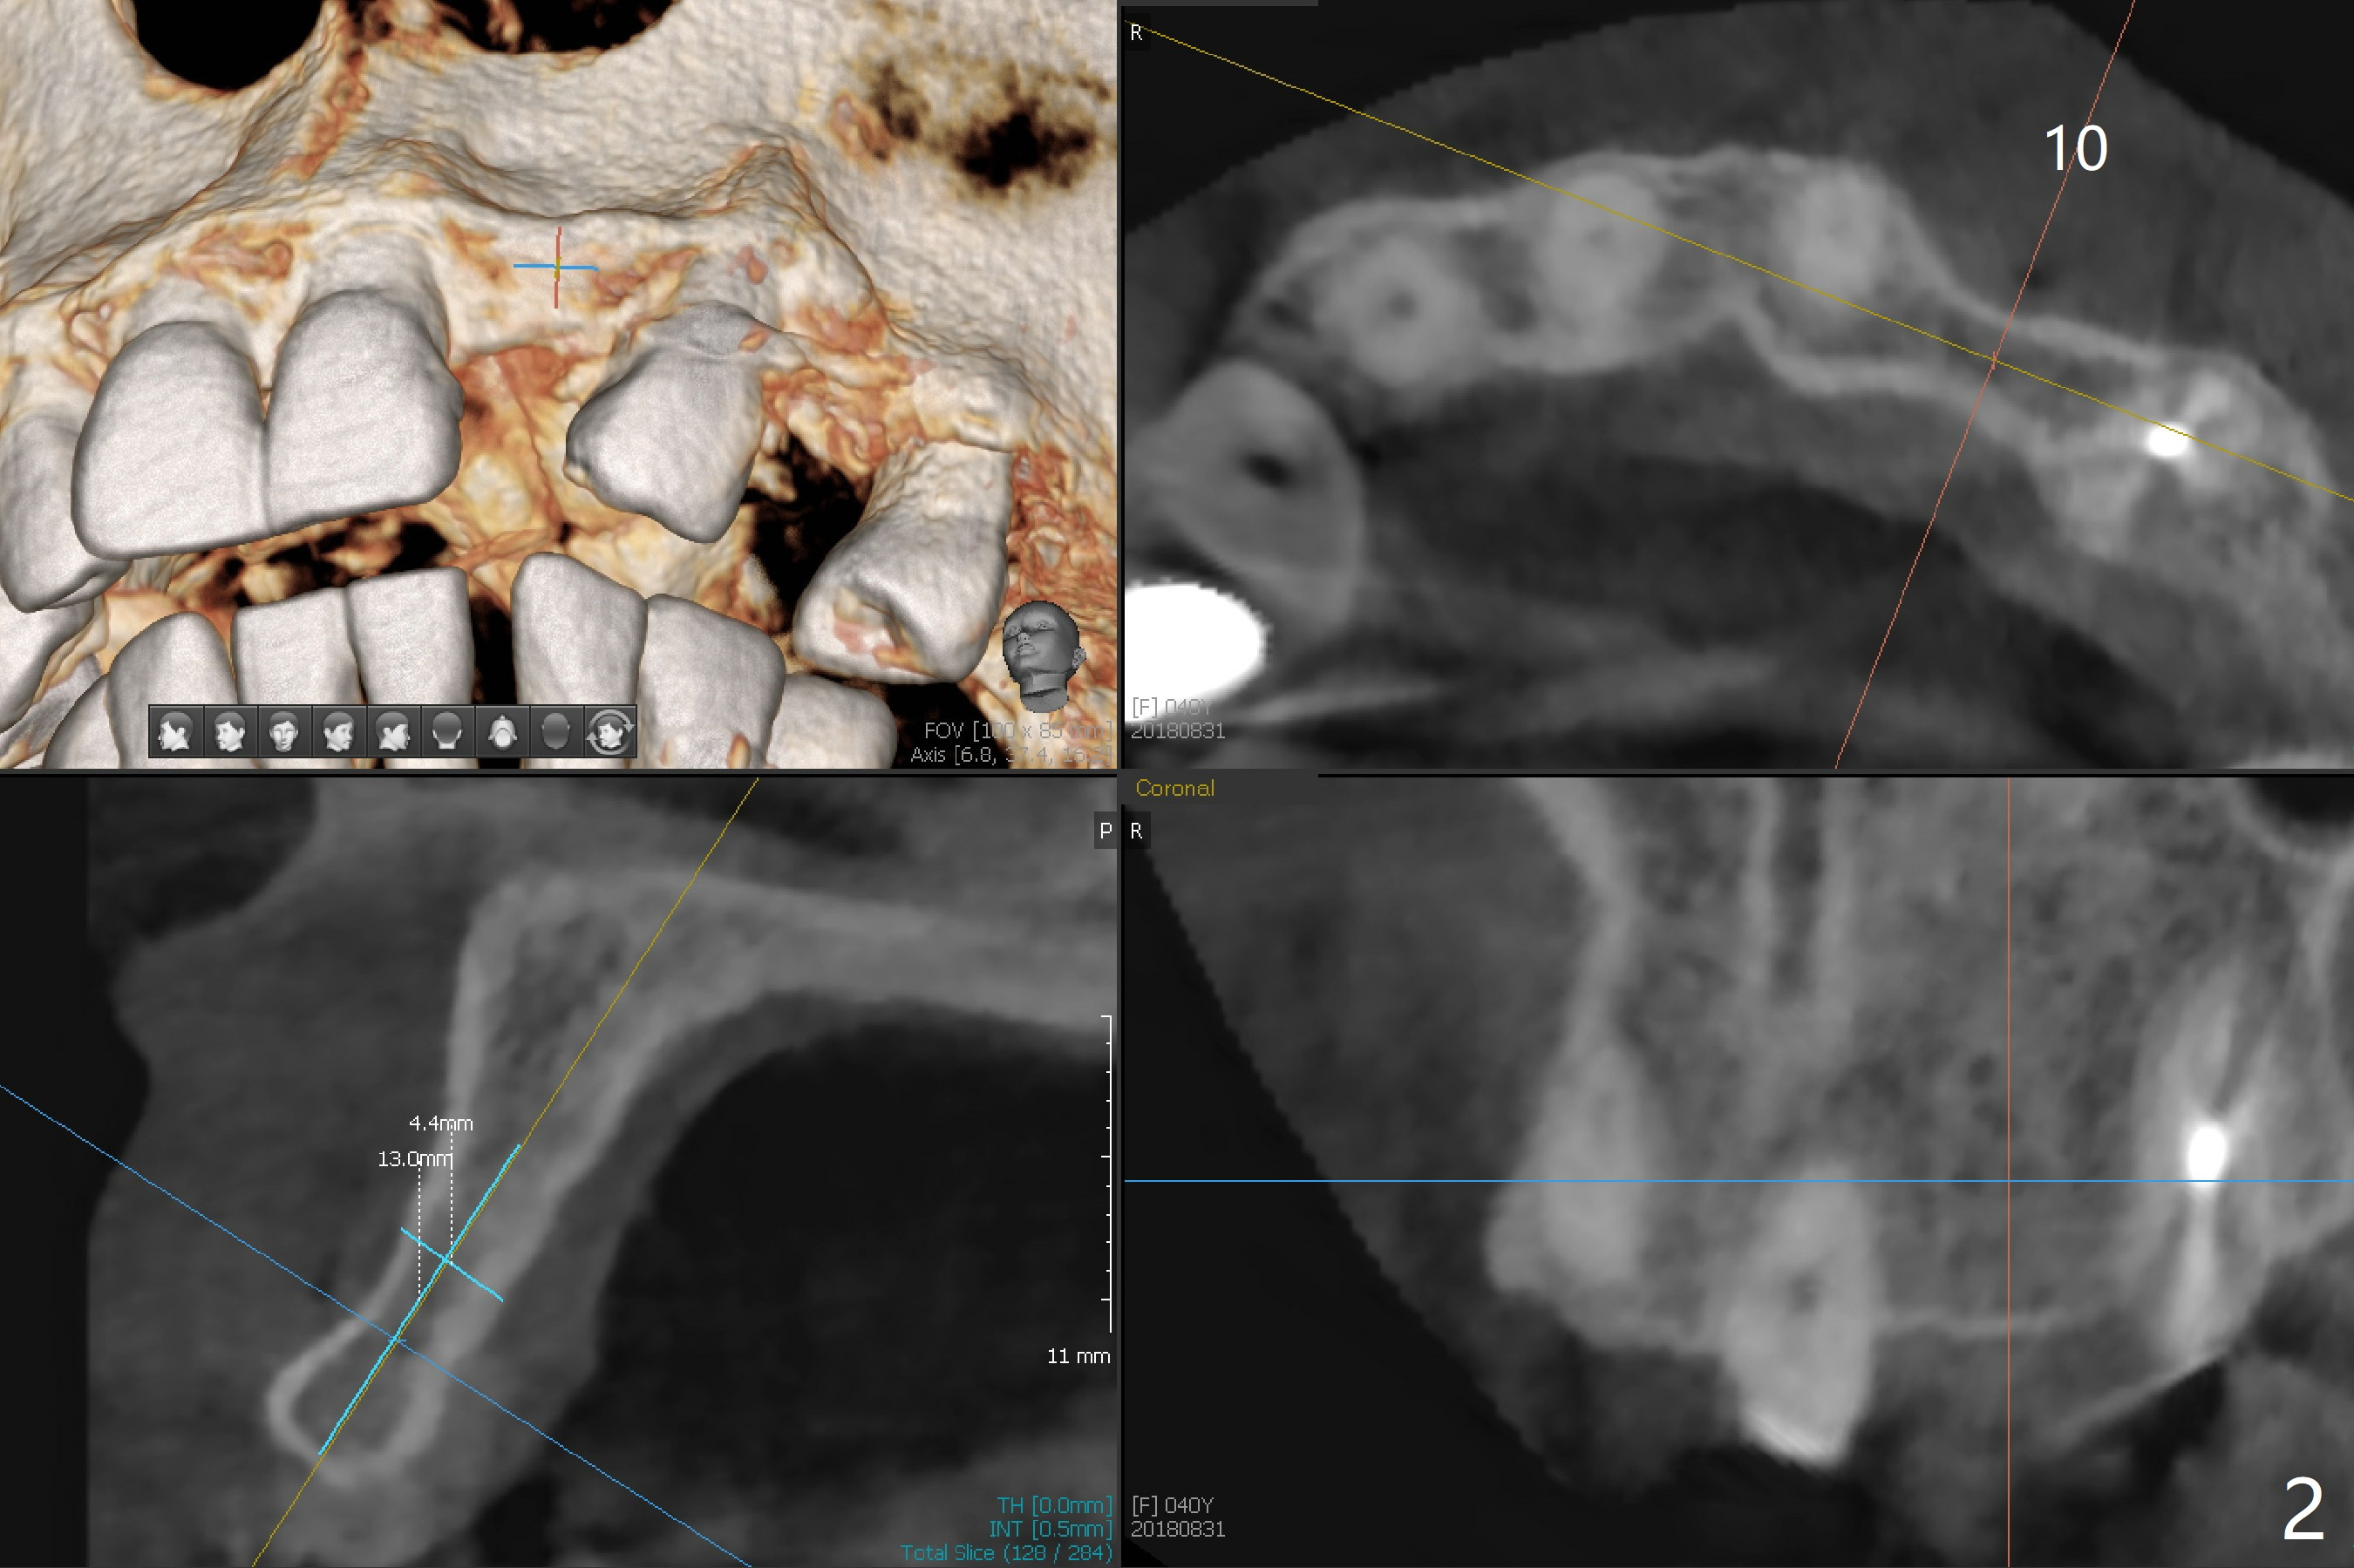

After cementation of implant crowns of #4 and 5, a  40-year-old skinny woman requests implants at #10 and 12 (Fig.1).  Since the ridge is narrow (Fig.2,3), narrow implants are required (2x12 and 3x10 mm).  As malpositioned implants at #4 and 5 were placed with free hand, guide is imminent for the new implants.

In fact, I want to place a 2 or 2.5x10-13 mm 1-piece implant.  Can you modify the protocol so that I can use pointed drill and possibly 2.2 mm one as long as possible without tissue punch or bone trimmer?  Help me go over the narrowest portion of the bone.  Then I use free hand technique.  Please help me as much as possible.  If it is difficult, can you ask your boss to modify the kit and work on the 1-piece implant?  I really hate to do this case, but the patient's flipper has been repaired several times.  Thanks.